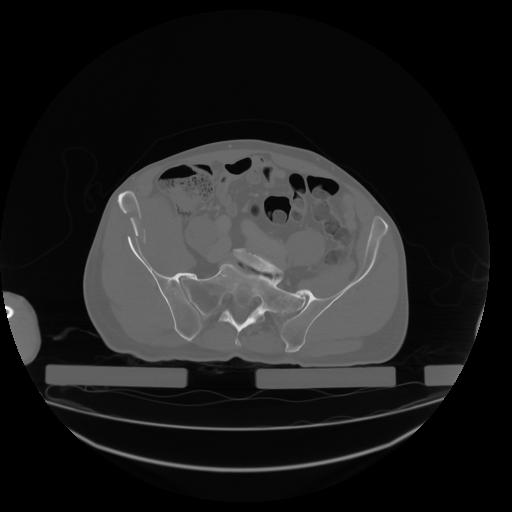

27 CUERPO,CE,Axial,3.0,CUERPO,,